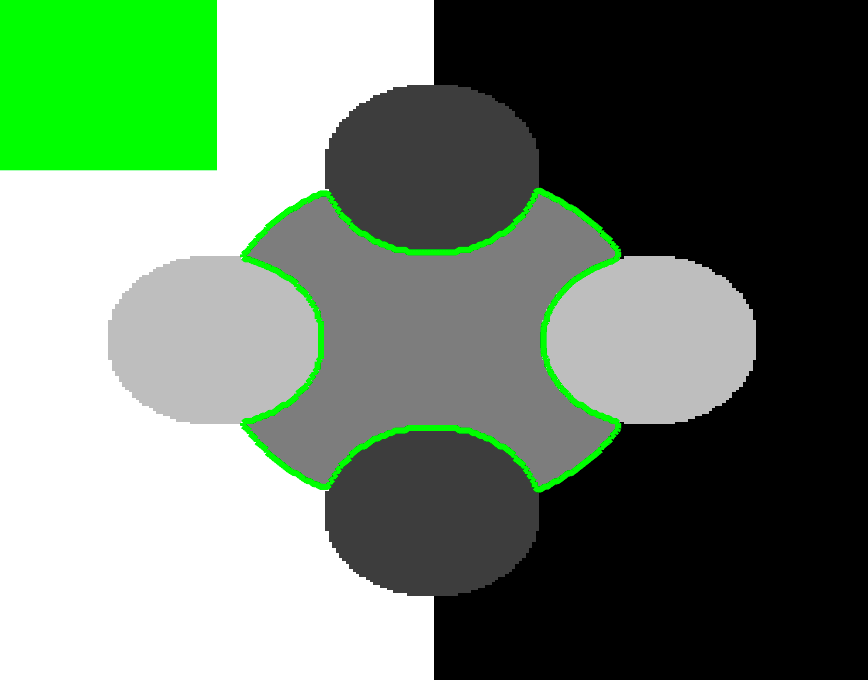

The motivation for this work comes from observing contradictions in using piecewise-constant intensity fitting terms in selective segmentation. Whilst good results are possible with this approach, the exceptional cases lead to severe limitations in practice. This is quite common in medical imaging as demonstrated in Fig. 1, where the target foreground has a low intensity. Given that the corresponding background includes large regions of low intensity, the optimal average intensities for this segmentation problem are and . For cases where , we see that by (1), almost everywhere in the domain . This means that it is very difficult to achieve an adequate result, without an over-reliance on the user input or parameter selection.

| (10) |

where is noise, is the characteristic function of the region , for respectively. The idea of selective segmentation is to incorporate user input to apply constraints that exclude regions classified as foreground, based on their location in the image. We use a distance constraint which penalises the distance from the user input markers. However, a key problem for selective segmentation is that for cases where the optimal intensity values and are similar, the intensity fitting term will become obsolete as the contour evolves. This is illustrated in Fig. 3. The purpose of our approach is to construct a model that is based on assumptions that are consistent with the observed image and any homogeneous target region of interest. A common approach in selective segmentation is to discriminate between objects of a similar intensity Rada:13 ; Geo ; CDSS . However, the fitting terms in previous formulations Klodt:13 ; Rada:13 ; Geo ; CDSS aren’t applicable in many cases as there are contradictions in the formulation in this context. We will address this in detail in the following section.

In this section we introduce the proposed data fitting term for selective segmentation. We consider objects that are approximately homogeneous in the target region. Intrinsically, it is then assumed that the region , provided by the user, is likely to provide a reasonable approximation of the optimal value and therefore an appropriate foreground fitting function, , is given by CV (2). For this reason, it makes sense to retain this term in the proposed approach. The contradiction is in how the background fitting function is defined. Considering piecewise-constant assumptions of the image, and many of the related approaches, the background is expected to be defined by a single constant value, . If then everywhere, and therefore the fitting term can’t accurately separate background regions from the foreground. It is not practical to rely on to overcome this difficulty as it will produce an over-dependence on the choice of and . This is prohibitive in practice. An alternative function must therefore be defined which is compatible with and . Here, we define a new data fitting term that penalises background objects in such a way that avoids these problems by allowing intensity variation above and below the value . In order to design a new functional, we first look at the original CV background fitting function

We define the proposed data fitting functional as follows:

for and as defined in (33). This is consistent with respect to the intensities of the observed object and the concept of selective segmentation. In Fig. 3 we see the difference between CV and the proposed fitting terms for given user input on a CT image. For the CT image, the CV fitting terms are near 0 within the target region. This is despite there being a distinct homogeneous area with good contrast on the boundary. This illustrates the problem we are aiming to overcome. With the proposed fitting term this phenomenon should be avoided in cases like this. By defining as in (33) there is no contradiction if the foreground and background intensities of the target region are similar.